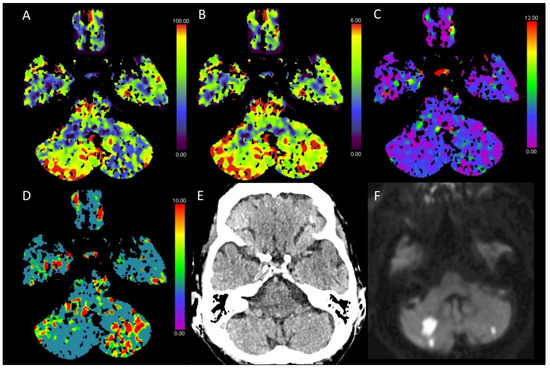

3.2. Acute Posterior Fossa Infarcts